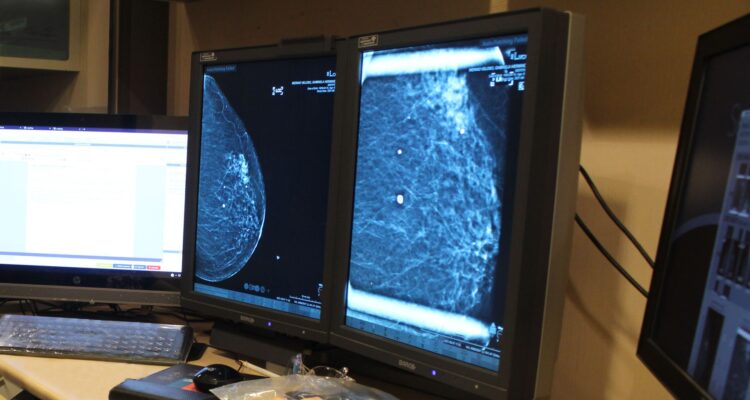

El Centro Regional de Diagnóstico de la Mama en el Hospital Las Higueras es el primero en ofrecer la Biopsia Esterotáxica con Contraste Endovenoso para la detección temprana de cánceres mamarios. Este método avanzado permite visualizar lesiones pequeñas, ofreciendo mayor precisión en el diagnóstico.

Hopital Las Higueras implementa tecnología de vanguardia para detectar cáncer de mamas